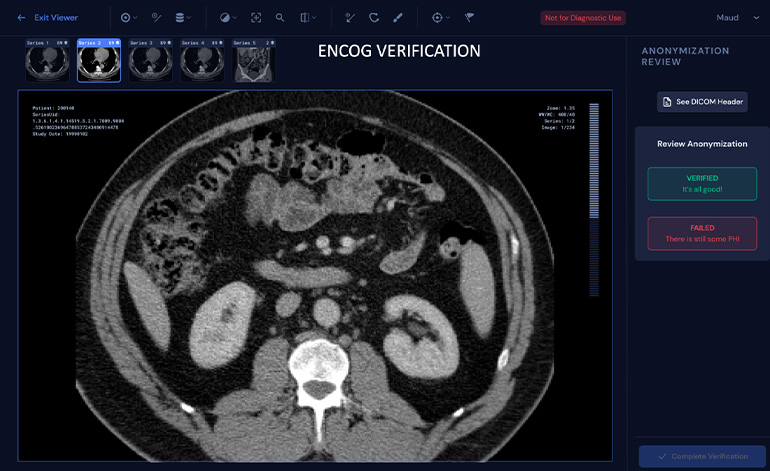

Enlitic relies on deep learning, computer vision, and natural language processing algorithms to develop diagnostics software across various imaging modalities. The company aims to build the ultimate tools for radiology to standardize, protect, integrate, and analyze image data. Their products Enlitic Curie, ENDEX, and ENCOG facilitate healthcare systems globally.

Source: Enlitic